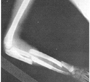

Fractura múltiplle bilateral

En este caso que observamos, presenta una fractura segmentaria de radio y otra de ulna, es un caso que fue maltratado. Al realizar el interrogatorio y no tener clara la evidencia de un accidente grave, dio la posibilidad de hacer el diagnóstico de un niño golpeado.